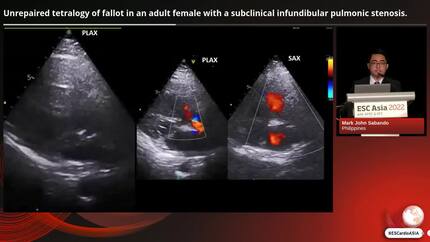

Unrepaired tetralogy of fallot in an adult female with a subclinical infundibular pulmonic stenosis.

Doctor M. Sabando (Manila, PH)